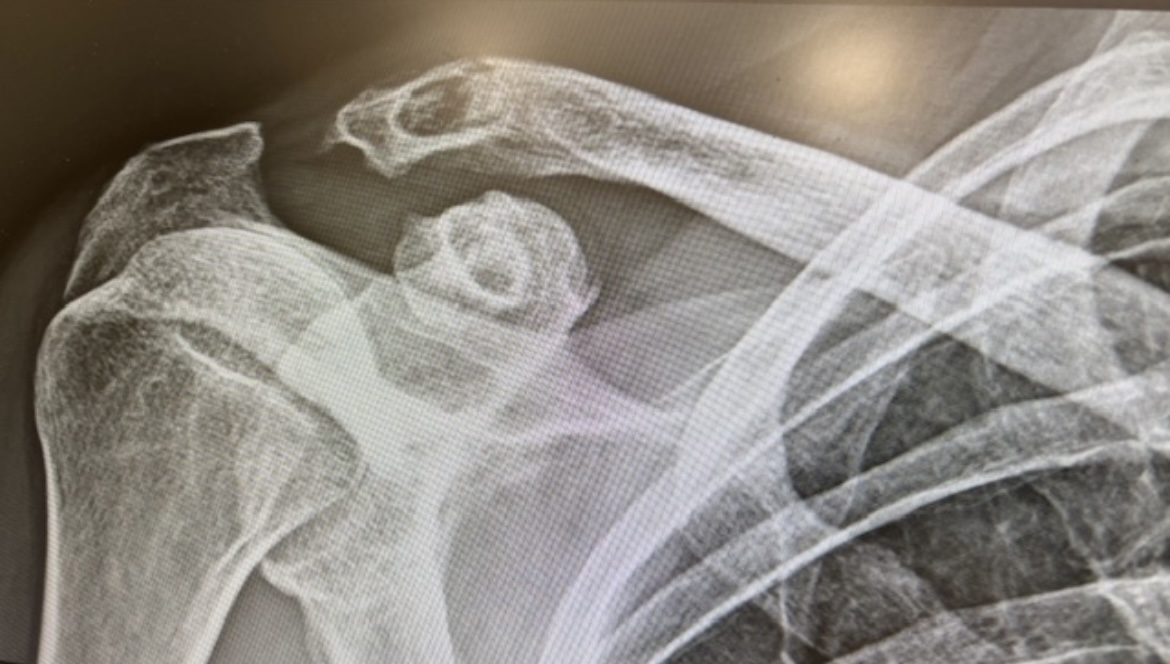

Hombre de 65 años fumador, dislipémico y con antecedente de luxación de articulación acromioclavicular hace 30 años por el que se realizó intervención quirúrgica. Presenta dolor y limitación de la movilidad en el hombro derecho tras caída de bajo impacto. Sin fiebre, pérdida de peso ni otros síntomas sistémicos.

Presenta fractura distal de clavícula no desplazada de bajo impacto sobre lesión osteolítica. Por lo que el diagnóstico diferencial de lesión osteolítica incluye: lesión secundaria a material quirúrgico implantado durante una cirugía de luxación acromioclavicular previa, artrosis por mala alineación residual o estrés mecánico crónico en la articulación, hiperparatiroidismo, gota tofacea, hipofosfatemia, proceso neoplásico, osteomielitis, tuberculosis, histiocitosis de célula de Langerhans, quiste óseo aneurismático y mieloma múltiple.

Realizar una evaluación radiográfica para distinguir la osteólisis de otras patologías. Solicitar una analítica para identificar déficits de vitaminas y minerales (como calcio y vitamina D) y descartar alteraciones endocrinas. Revisar estudios previos del paciente. El tratamiento incluye inmovilización, analgesia, rehabilitación y si es necesario cirugía.

Las intervenciones quirúrgicas que utilizan bandas o dispositivos de fijación suspensoria ajustables pueden causar la erosión ósea de la clavícula, debido al roce continuo o presión del dispositivo, y las posteriores fracturas distales de la clavícula tardías. La fisioterapia y la inmovilización correcta son cruciales en el manejo de las fracturas especialmente para prevenir complicaciones como la capsulitis adhesiva. Como medidas presentivas en fractura ósea de bajo impacto incluye la evaluación de la vitamina D, monitorización de la función renal y densiometría ósea. Además, se destaca la importancia del abordaje integral y el enfoque multidisciplinario.